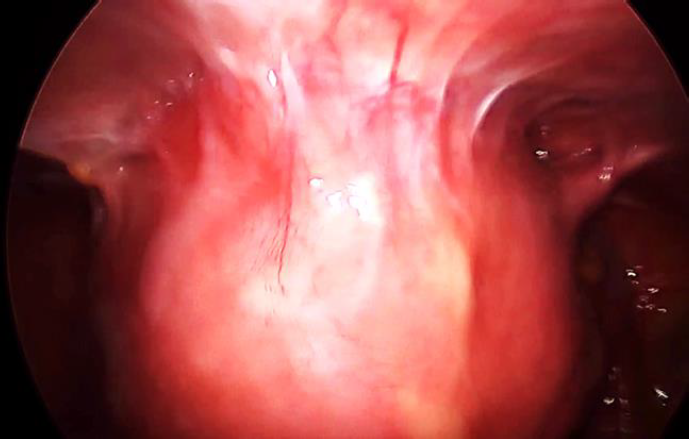

The preoperative haemoglobin was 10 gr % and the rest of the testing was normal, thereby the procedure was scheduled. Four trocars were placed: a 10 mm optic trocar at 4 cm above the umbilicus, two 5 mm left lateral and one 5 mm right lateral. The abdominal CO2 pressure was kept at 15 mm Hg. As findings, the uterus was densely adhered to the anterior abdominal wall (Figure 2) with the ovaries and the tubes normal.

The pouch of Douglas was free of adhesions. As ultrasound showed that the bladder was 2,05 cm lower down compared to the lowest inferior adherend part of the uterus, its dissection from the anterior abdominal wall was conducted without particularity leaving the fat above on the anterior abdominal wall and continuing close to the uterine wall (Figure 2).

This dissection evolved concomitantly with the separation of the adnexa and the opening of the broad ligament. The bladder was partially filled with normal saline to optimize its recognition during dissection. Hysterectomy was performed using a lateral approach opening the left paravesical space (Figure 3), that allowed to enter the vesicovaginal space from the left and to dissect into this space. At that point, the left uterine artery was easily coagulated and cut and as the adhesions were situated only in the anterior aspect of the pelvis, there was no need to first isolate the ureter to secure it.

Fig. 2a: Uterus adhered to the anterior abdominal wall.

Fig. 2b: Dissection of the uterus adherend to the anterior abdominal wall. Dissection is carried out on the line between the fat and the uterine wall

Fig. 3: Dissection of the bladder. Obliterated umbilical artery, left medial paravesical space and vesicovaginal space are shown.